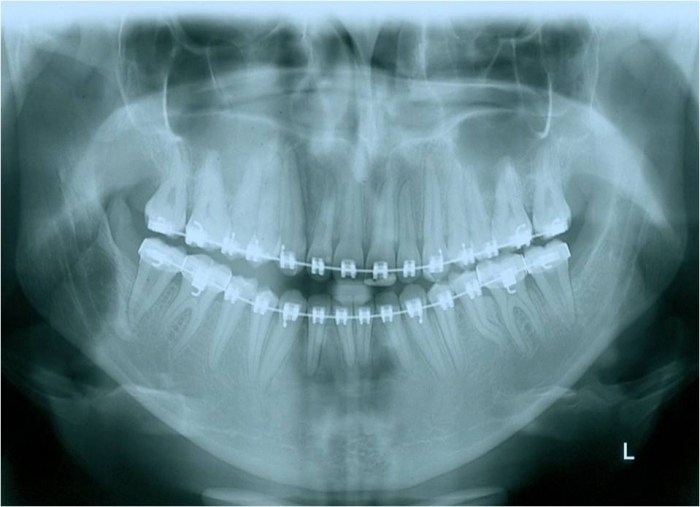

Raio x panorâmico inicial - Clínica Cliniface

Raio x panorâmico inicial